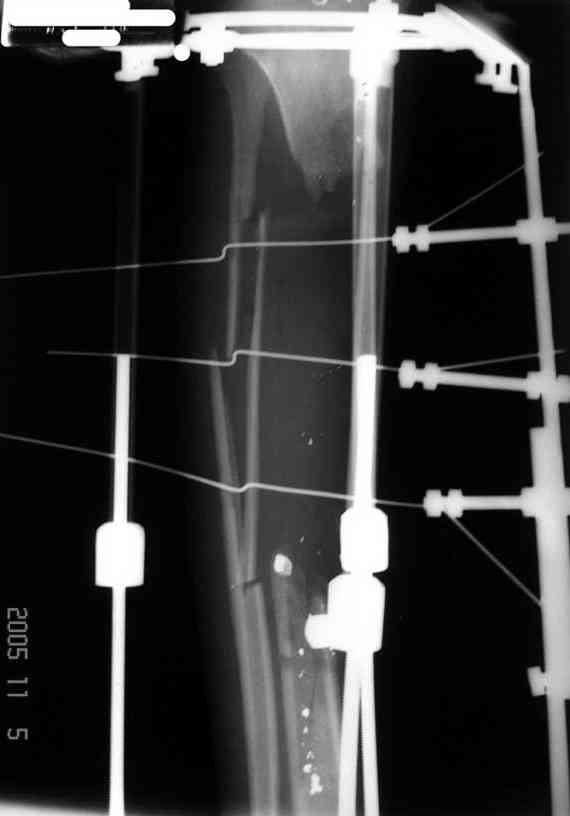

Re: Дефект большеберцовой кости - что делать? Ваше

У нас не задумываясь провели бы vascularized fibular graft.

Можно было split fibula transfer, но для этого

необходима интактная малоберцовая.

Предложенный Александром вариант, кейдж плюс стержень - неплохая идея, уменьшает срок восстановления, и без наружных атрибутов фиксатора.

Хотя для уменьшения размера дефекта (кейдж) можно было предложить предварительную однофокальное удлинение в проксимальном метафизе, потом применение стержня.

Стержень можно забить через голеностоп в таран, тогда удлинится и усилится короткий дистальный конец.

Если смелость больной достаточна для аппаратного лечения, тогда другой вариант, комбинация удлинения в проксимальном отделе большеберцовой и утолщения малоберцовой в нижней трети, где диаметр малоберцовой позволяет.

Для сокращения времени малоберцовую можно расширить быстрыми темпами, а в образовавшуюся щель ввести костный графт.